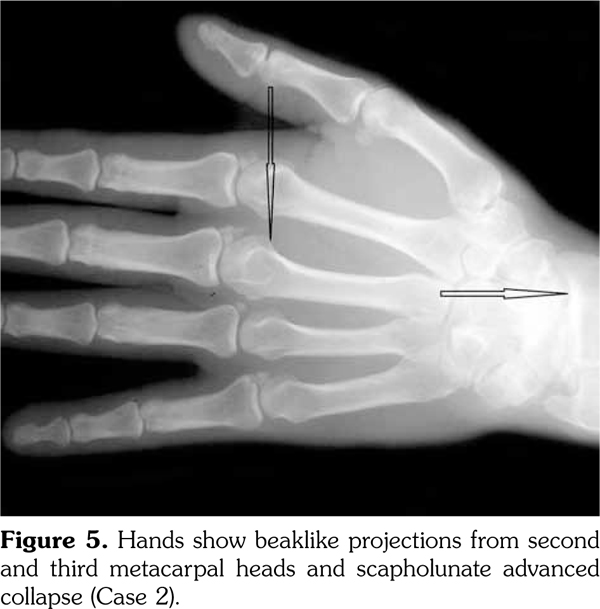

Case 2- A 39-year-old male patient presented with swelling of both knee joints. He also gave a history of recurrent painful swelling of knee joints and wrist joints for more than 10 years and was treated by an Ayurvedic physician. Other medical history or family history of medical problems were insignificant. There was a massive swelling of both knee joints with effusions, which was aspirated and the X-rays revealed calcification of the articular cartilages (Figure 5). A written informed consent was obtained from the patient.

His hand X-rays showed hook like projections arising from radial aspect of second and third metacarpal heads with scapholunate advanced collapse and indentation of distal radius by the scaphoid bone. It also showed CC of the triangular fibrocartilage (Figure 6).

He had chondrocalcinosis involving the menisci and hyaline cartilage, with predominant patellofemoral joint osteoarthritis. His blood investigations to find a metabolic cause for CC were negative.